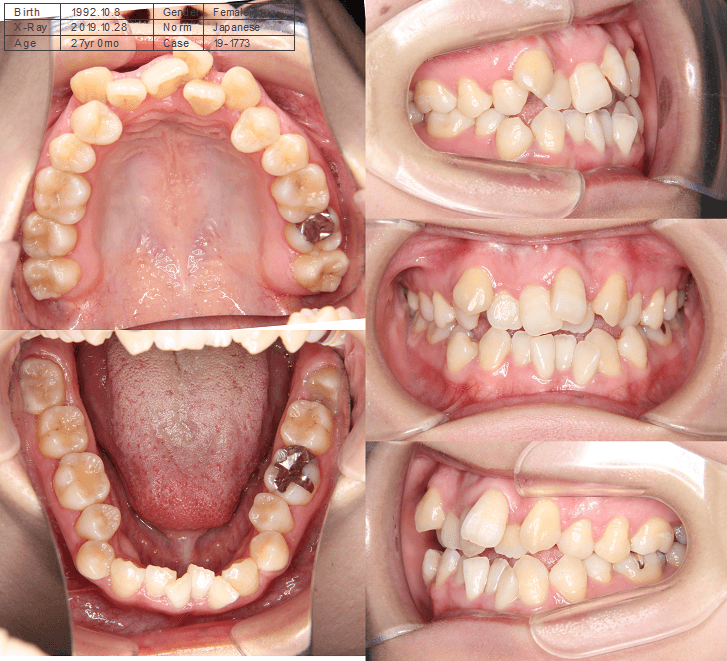

開咬と口元の突出感が気になる

| 年齢・性別 | 22歳の女性 |

|---|---|

| 主訴 | 上下顎前歯部に開咬と口元の突出感を気にされて来院された。咬み合わせや審美的な改善を希望されていました。 |

| 治療期間・回数 | 3年9ヶ月・32回 |

| 費用 | 930,000円 |